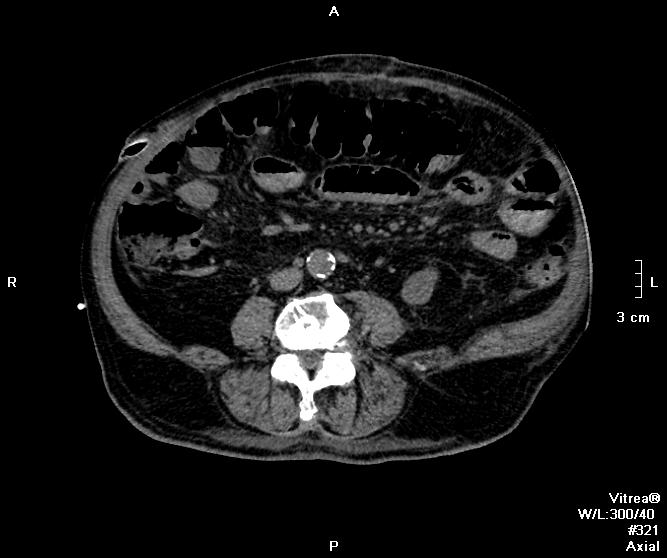

Пациент оперирован по поводу аденоКа толстого кишечника, гемиколэктомия. Онкопоиск, поиск вторичного поражения.

В воротах печени беда, но не об этом сейчас. Прицельно смотрим контраст.

Артериальная.

Венозная.

отсроченные

Во втором случае наблюдается гиподенсный участок в печени.

дифференцируем между метастазом и холангиокарциномой

Случай 1. Атеросклероз сосудов, запаздывание фаз секунд на 20-25. Получили раннюю артериальную фазу (посмотрите контрастирование камер сердца). И вместо портальной - нечто между поздней артериальной и портальной. Стоило, как мне кажется, сделать 85-90 сек, тогда бы попали в порталку.

Случай 2. Опять не попали в фазы, рано. Исследование малоинформативно по сути(. Какова скорость введения автошприцем? Катетер кубитальный или в запястье?